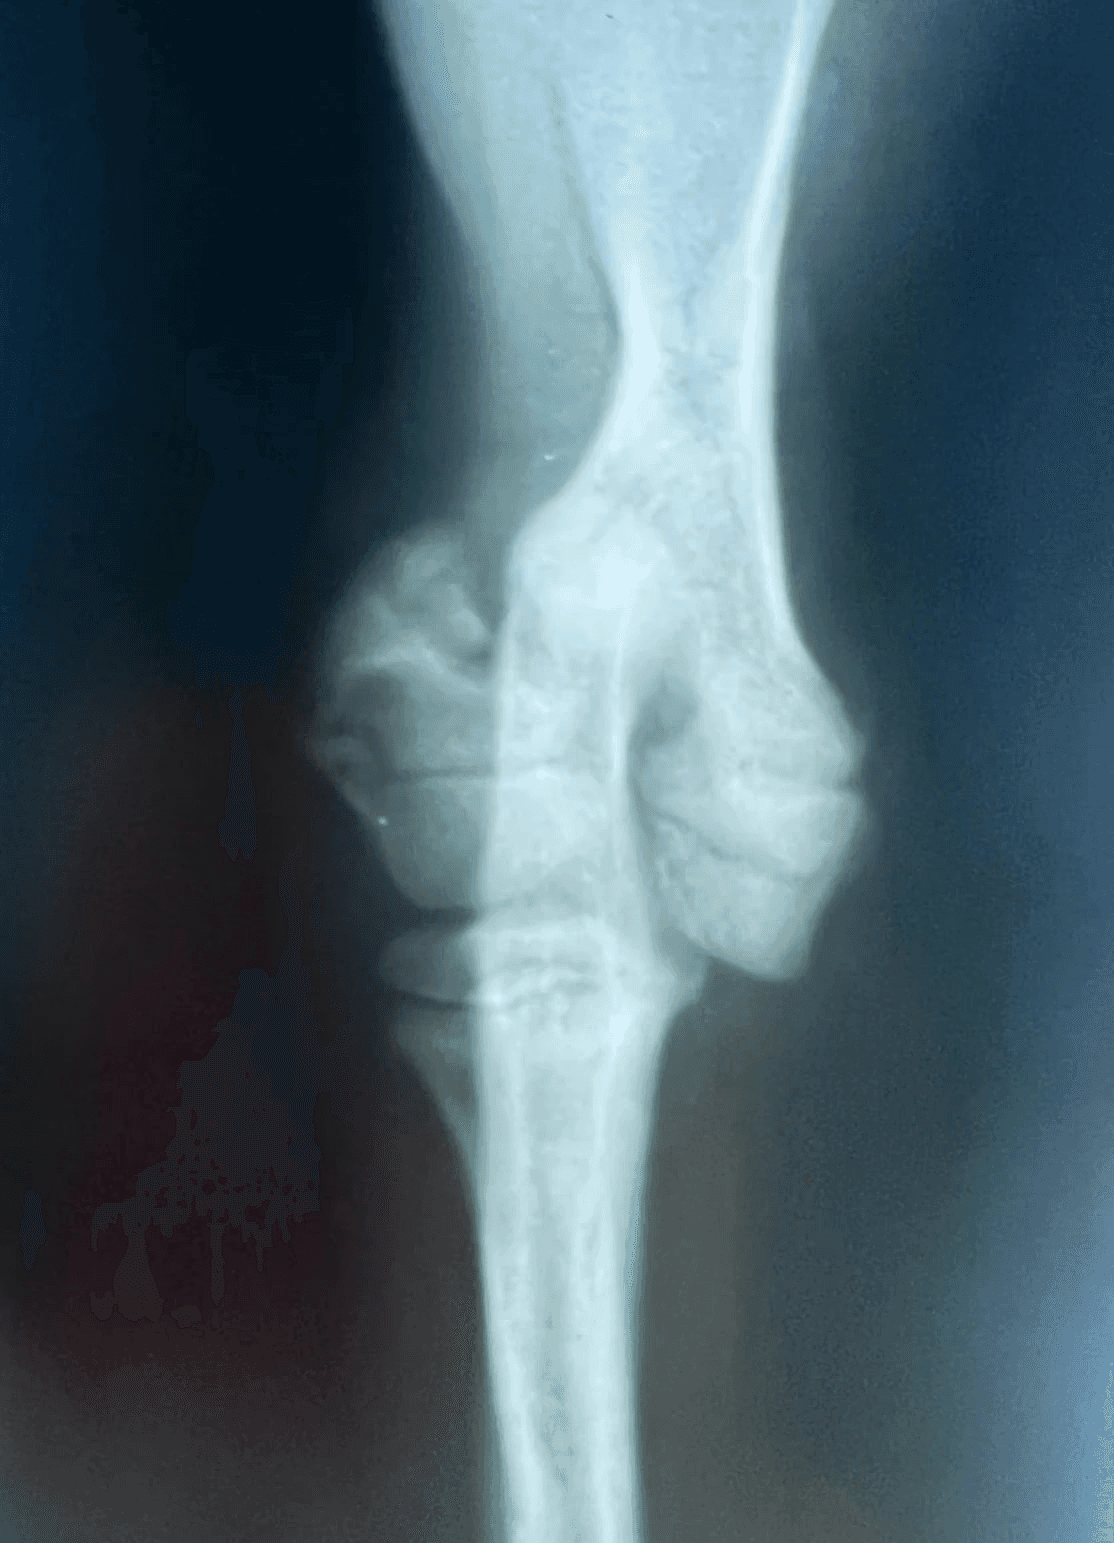

Screws, Pins and Wire

When fragments are very small or near the joint, we are limited to using small implants. These are relatively weak and more prone to failure or loosening. Often a bandage will be used post-operatively to help protect these repairs.

Articular humeral fracture in a puppy

Growth Plate tibial fracture in a puppy